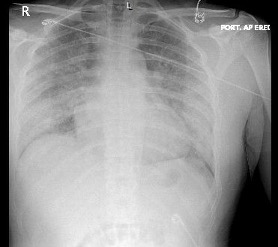

A chest radiography scan was conducted, results of which showed patchy air space opacities (Figure 1). A computed tomography (CT) angiogram of the chest showed no pulmonary embolus but did show bilateral, diffuse ground-glass opacities (Figure 2). Results of a urine drug screen were positive for tetrahydrocannabinol (THC). SARS-CoV-2 RNA NAAT run on cepheid PCR was negative.

This patient’s clinical presentation, imaging, and laboratory results were consistent with acute pneumonia. Thus, bacterial or viral infection needed to be ruled out, and empiric antibiotics were appropriate. Common respiratory pathogens—including Streptococcus pneumoniae, Mycoplasma pneumoniae, Legionella pneumophila, and influenza A and B during flu season— should be ruled out.1 In addition, given the high level of inflammatory markers, hypoxia, and elevated D-dimer level, pulmonary embolism had to be ruled out as well, which was achieved via the CT angiogram of the chest. This CT showed diffuse ground glass opacities, which are found in patients with both COVID-19 and EVALI. However, there was subpleural sparing (Figure 2), which is more consistent with EVALI.6 Furthermore, nausea and weight loss are commonly associated with EVALI.4